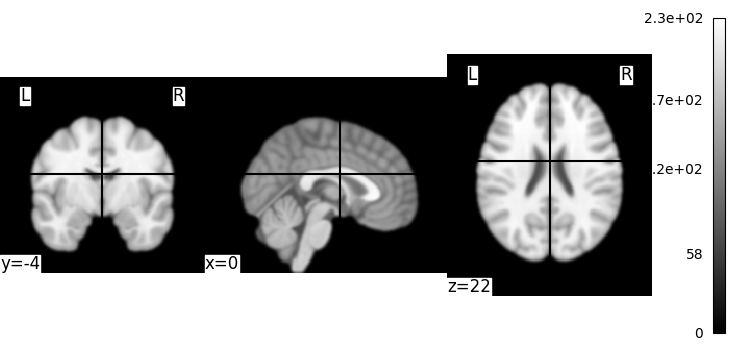

Simple image manipulation: smoothing¶

Let’s use an image-smoothing function from nilearn:

smooth_img

Functions containing ‘img’ can take either a filename or an image as input.

Here we give as inputs the image filename and the smoothing value in mm

from nilearn import image

smooth_anat_img = image.smooth_img(MNI152_FILE_PATH, fwhm=3)

This is an in-memory object. We can pass it to nilearn function, for instance to look at it

<nilearn.plotting.displays._slicers.OrthoSlicer object at 0x75879167b7c0>